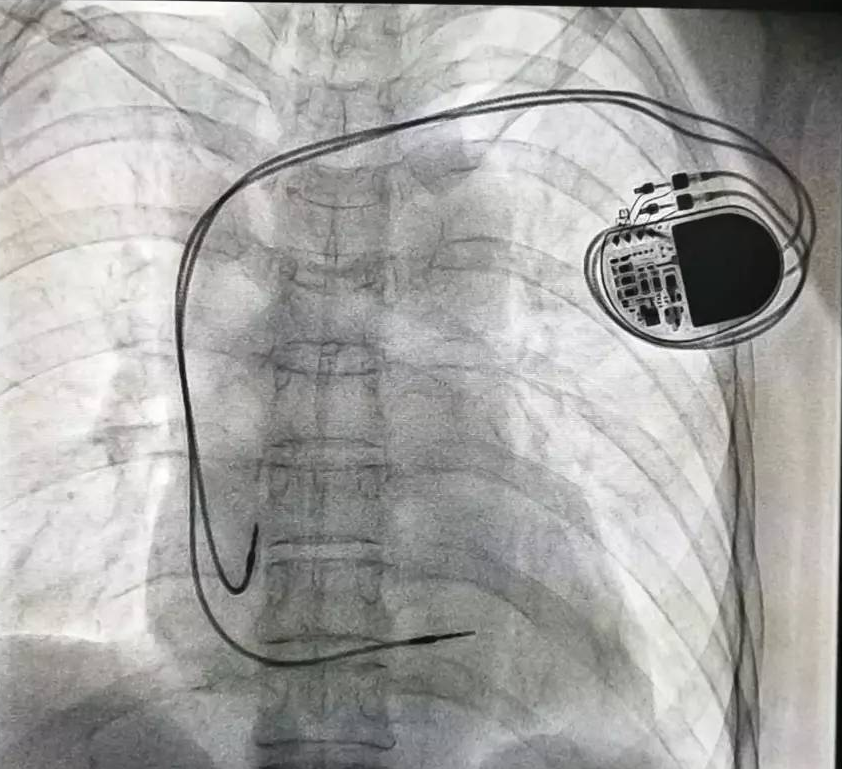

相較于傳統(tǒng)的起搏治療,Micra體積僅有維生素膠囊大小,體積比傳統(tǒng)心臟起搏器減小93%,重量僅約2克。它可通過微創(chuàng)方式植入心臟內,無導線、無囊袋,患者甚至感覺不到他的存在。

器械之家曾做過專題報道的“世界最小起搏器”(嬰兒用除外)在經(jīng)過了漫長的中國本土臨床研究后,終于獲得NMPA批準,正式于中國上市!